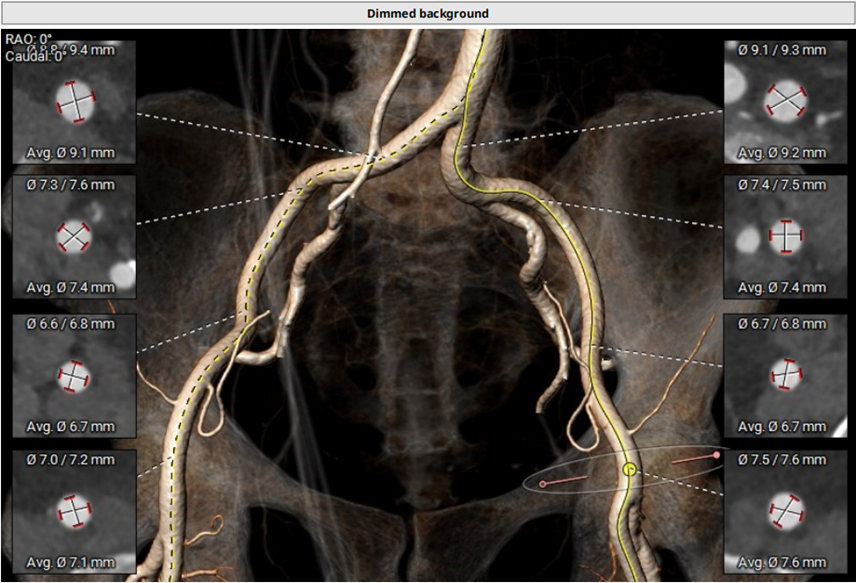

血管入路评估

血管入路评估